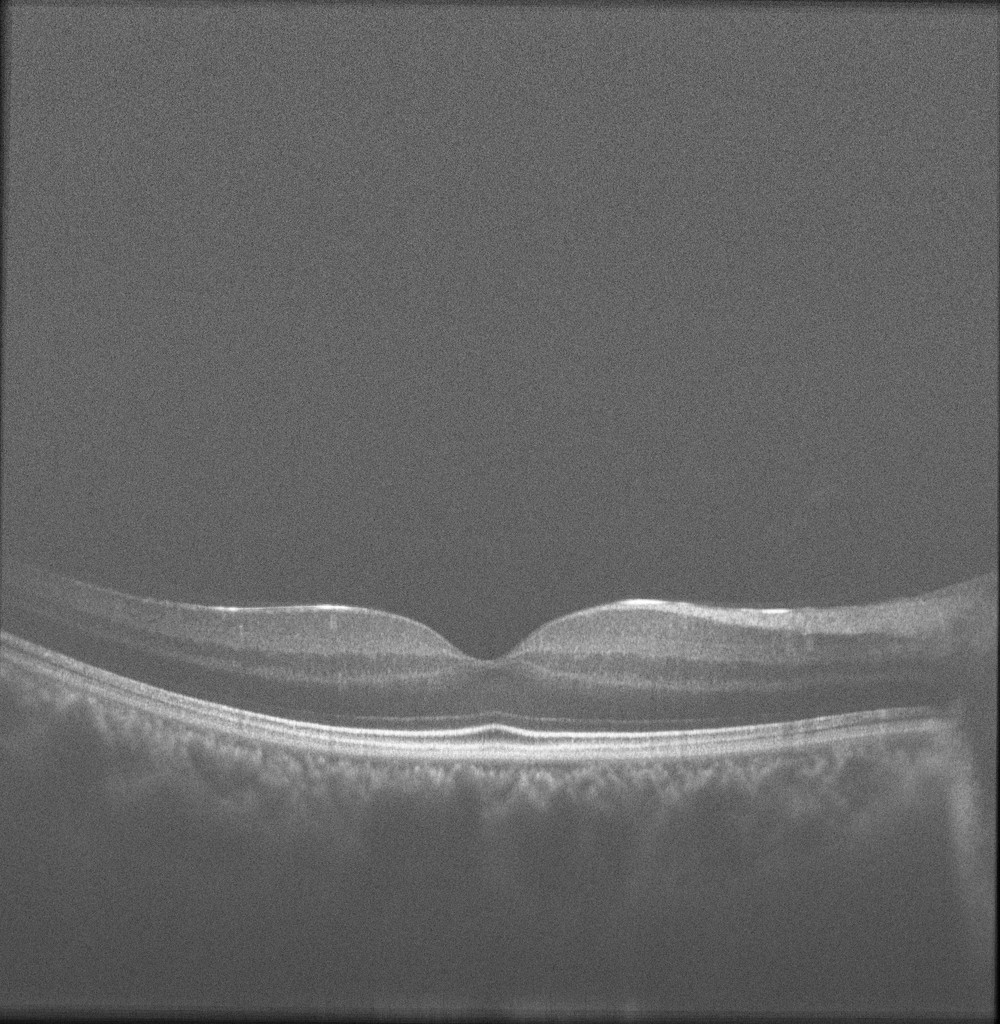

There are several different applications for using image registration approaches in OCT image analysis. One of the basic applications is in speckle noise reduction. As mentioned in Section 3, hardware-based noise reduction techniques take the average of several uncorrelated scans in order to reduce the noise. The same thing can happen after finishing image acquisition too. The main idea is to gather several images of the same cross-section in retina, register them together and take the average. Having a small movement in the eye provides us with an uncorrelated pattern of speckle. Having N𝑁N B-scans, the SNR can be improved by a factor of N𝑁\sqrt{N}. In [61] a dynamic programming based method is used for compensation of the movements between several B-scans and reducing the speckle noise. A hierarchical model-based motion estimation scheme based on an affine-motion model is used in [62] for registering multiple B-scans to be used for speckle reduction. Fig. 6 shows the result of affine registering the images from close locations in retina and averaging. Recently, the use of low-rank/sparse decomposition based batch alignment has been investigated for speckle noise reduction in OCT images too. Taking advantage of Robust Principal Component Analysis (RPCA) [63] and simultaneous decomposition and alignment of a stack of OCT images via linearized convex optimization, better performance is achieved in comparison to previous registration based denoising techniques. For more details on the method and results, the reader is referred to [64, 65]

Refer to caption

Figure 8: Result of averaging affine registered cross-sections from close location in retina